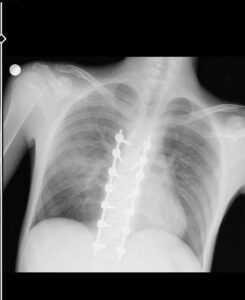

YUSUF GÜNDOĞMUŞ’UM VÜCUDUN TAKILAN PLATİNLER (BAHADIR TURGUT/ESKİŞEHİR-İHA)

“Beş gün entübe edildi. Ne olacağı belli değildi çıkmama ihtimali vardı. Şükürler olsun doktorlarımız ve Rabbim sayesinde entübeden çıktık. Hatta ciğerin birisinde infilak vardı; ciğer sorunumuzdan dolayı özellikle yoğun bakımda entübediydik. Beş günün sonunda ciğerleri toparlamaya başladı; entübeden çıkarttılar. Solunumu normale döndü. Sırayla sağlığı yerine gelmeye başladı. Bir hafta sonra kolundan ameliyat oldu platin koydular. Omurilikten ameliyat olduk. Omuriliğinde ilk röntgende tek kırık gördüler; üç kemiği birbirine bağlayacaklardı. Sonradan ikinci röntgende üç kırık olduğunu gördük; yedi kemiği birbirine bağladılar. Omuriliğe platin takıldı. 14 tane civatamız var. Şükürler olsun doktorlarımıza, Allah razı olsun. Evladımız gayet iyi, sağlıklı, yerinde. Artık işte suratta, çenede, burunda, elmacık kemiklerinde parçalı kırıklarımız var. Osman Gazi Fakültesi’nde Allah’ın izniyle buradaki hocalarımıza, önce Rabbim’e sonra hocalarımıza emanet çocuğumuz. İnşallah daha iyi olacağız; ben kendi adıma söylüyorum. Çocuğuma, her motora bindiklerinde sürekli kask ve montlarını giymelerini tembihliyordum. Giymediklerinde fırça atıyordum. Eskişehir’de birçok yerde tanınırız, tanırlar. Sevenimiz, eşimiz, dostumuz çok; uyarırlar, telefon gelir, haber verirler. Her duyduğumda, gördüğümde söylerim. Sağ olsun, çocuğum da o gün beni dinlemiş, kaskını takmış. Şükürler olsun ki takmış; takmasaydı o gün, o kazada belki çocuğumuzu kaybederdik